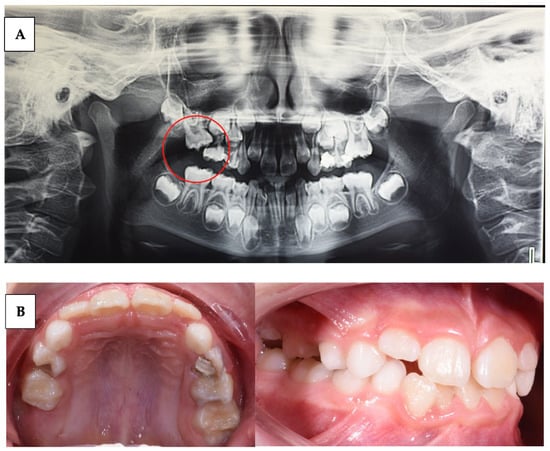

| Wagner et al. (2023) [59] | Case series | 3 | Describe the variability of clinical presentations of PFE associated with pathogenic variants of PTHR1 | Clinical examination, radiological examination, and molecular DNA testing | Multidisciplinary complex treatment, from child to adulthood. |